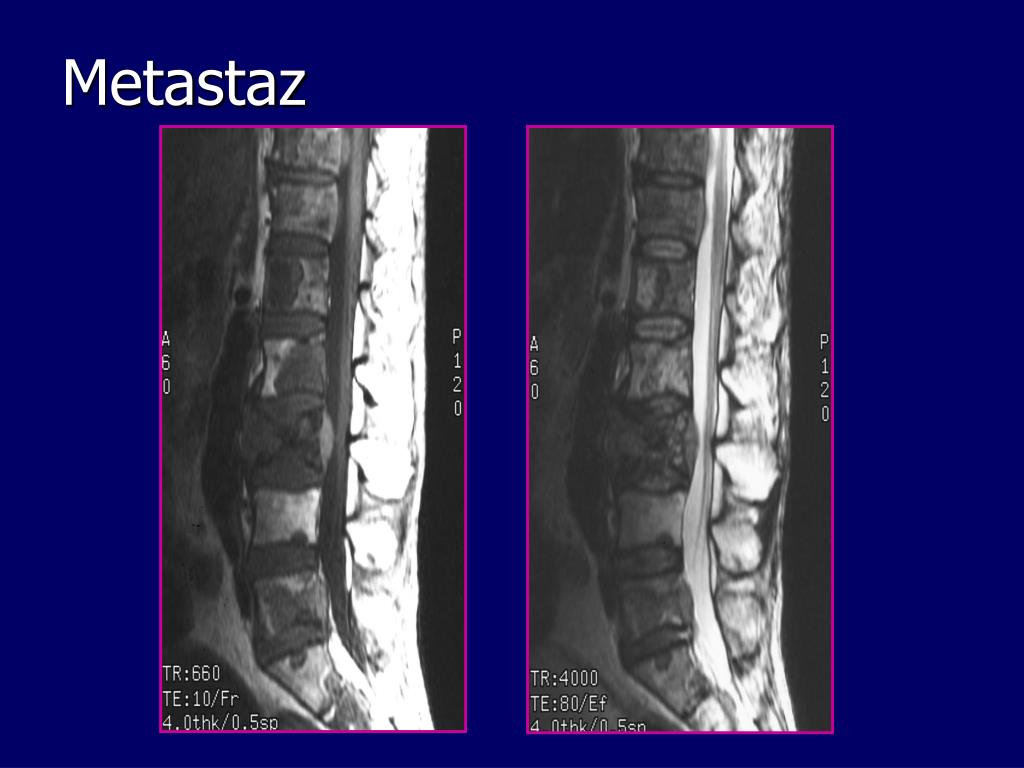

18. Metastaz